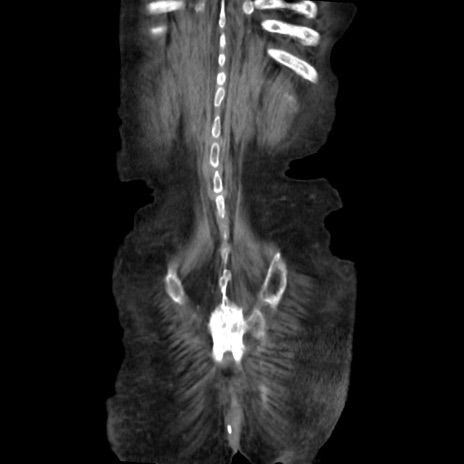

矢状断像